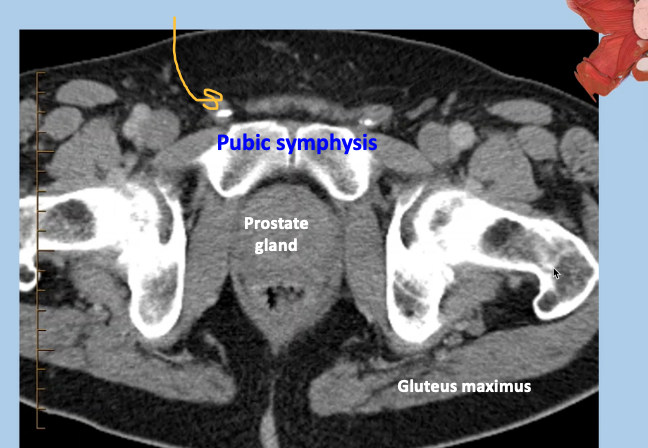

CT male pelvis, axial view

Calcification within the vascular structures; small bit of calcifications in vas deferes